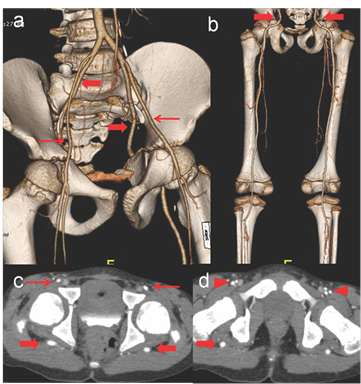

CT angiographic evaluation of the bilateral lower limbs demonstrated internal iliac arteries continuing as sciatic arteries (exiting though greater sciatic foramen with a posterior course) till popliteal fossa and dividing into normal anterior tibial artery and tibio-peroneal trunk. No associated aneurysm, stenosis or calcific plaques were noted. External iliac arteries were continuing as profunda femoris and incomplete superficial arteries (Figure 1). Findings were in keeping with complete bilateral persistent sciatic arteries with incomplete femoral arteries (Type III of Ahn-Min classification). The findings were discussed with the patient and no treatment was offered as there were no signs of limb ischemia or any associated abnormalities.

Figure 1 CT Angiography volume rendered images in anterior (a) and posterior projections (b) showing bilateral persistent sciatic arteries continuing as internal iliac arteries and coursing through the bilateral sciatic foramina (thick arrows) which are supplying the entire vascular axis of the leg (complete SPAs). The external iliac artery is continuing as CFA (thin arrows) which are continuing as incomplete superficial and profunda femoris arteries. Axial CT angiographic images at level of femoral head (c) and neck of femur (d) show posterior course of PSAs in the gluteal regions (thick arrows). The external iliac (thin arrows) and the profunda femoris (arrowheads) arteries are anterior and normal in course.